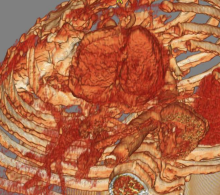

Two large clinical trials were presented in the late-breaking clinical trials session at the American College of Cardiology's (ACC) 61st Annual Scientific Session this week that indicate coronary computed tomography angiography (CCTA) used as a tool to evaluate patients with chest pain in the emergency department is safe, time-efficient and cost-effective, compared to the current standard approach.

Coronary angiography is unable to accurately predict the severity of vessel narrowing, suggesting fractional flow reserve (FFR) functional tests should be added to help determine if a patient needs revascularization. This was according to research presented from the IRIS FFR-DEFER trial at the American College of Cardiology's (ACC) 61st Annual Scientific Session this week in Chicago.